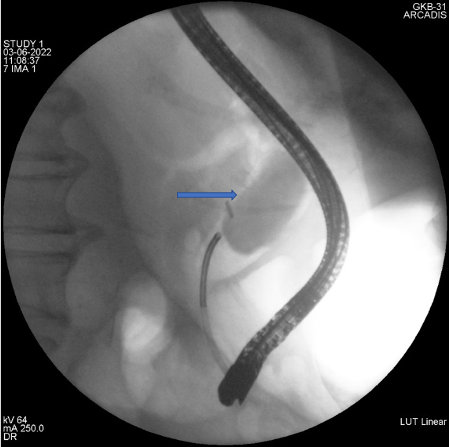

Представлено клиническое наблюдение успешного этапного эндоскопического лечения при гигантском множественном холедохолитиазе. Традиционное хирургическое вмешательство было противопоказано пациентке ввиду выраженных сопутствующих заболеваний и большого анестезиологического риска. Базовым методом мини-инвазивного лечения была контактная литотрипсия, дополненная баллонной дилатацией зоны эндоскопической папиллосфинктеротомии и механической внутрипротоковой литотрипсией. Применение контактной литотрипсии при пероральной транспапиллярной холангиоскопии в сочетании с другими современными способами эндоскопического лечения холедохолитиаза обладает хорошим техническим и клиническим эффектом даже при гигантских размерах билиарных конкрементов.

Будзинский С.А., Шаповальянц С.Г., Воробьева Е.А., Козлова П.С., Соловьев Н.С., Платонова Е.Н., Федоров Е.Д. Успешное эндоскопическое лечение гигантского множественного холедохолитиаза с применением пероральной транспапиллярной холангиоскопии и внутрипротоковой контактной литотрипсии. Анналы хирургической гепатологии. 2023;28(1):109-115. https://doi.org/10.16931/1995-5464.2023-1-109-115

Budzinskiy S.A., Shapovalyants S.G., Vorobyova E.A., Kozlova P.S., Solovjev N.S., Platonova E.N., Fedorov E.D. Successful endoscopic treatment of giant multiple choledocholithiasis using oral transpapillary cholangioscopy and intraductal contact lithotripsy. Annaly khirurgicheskoy gepatologii = Annals of HPB Surgery. 2023;28(1):109-115. (In Russ.) https://doi.org/10.16931/1995-5464.2023-1-109-115